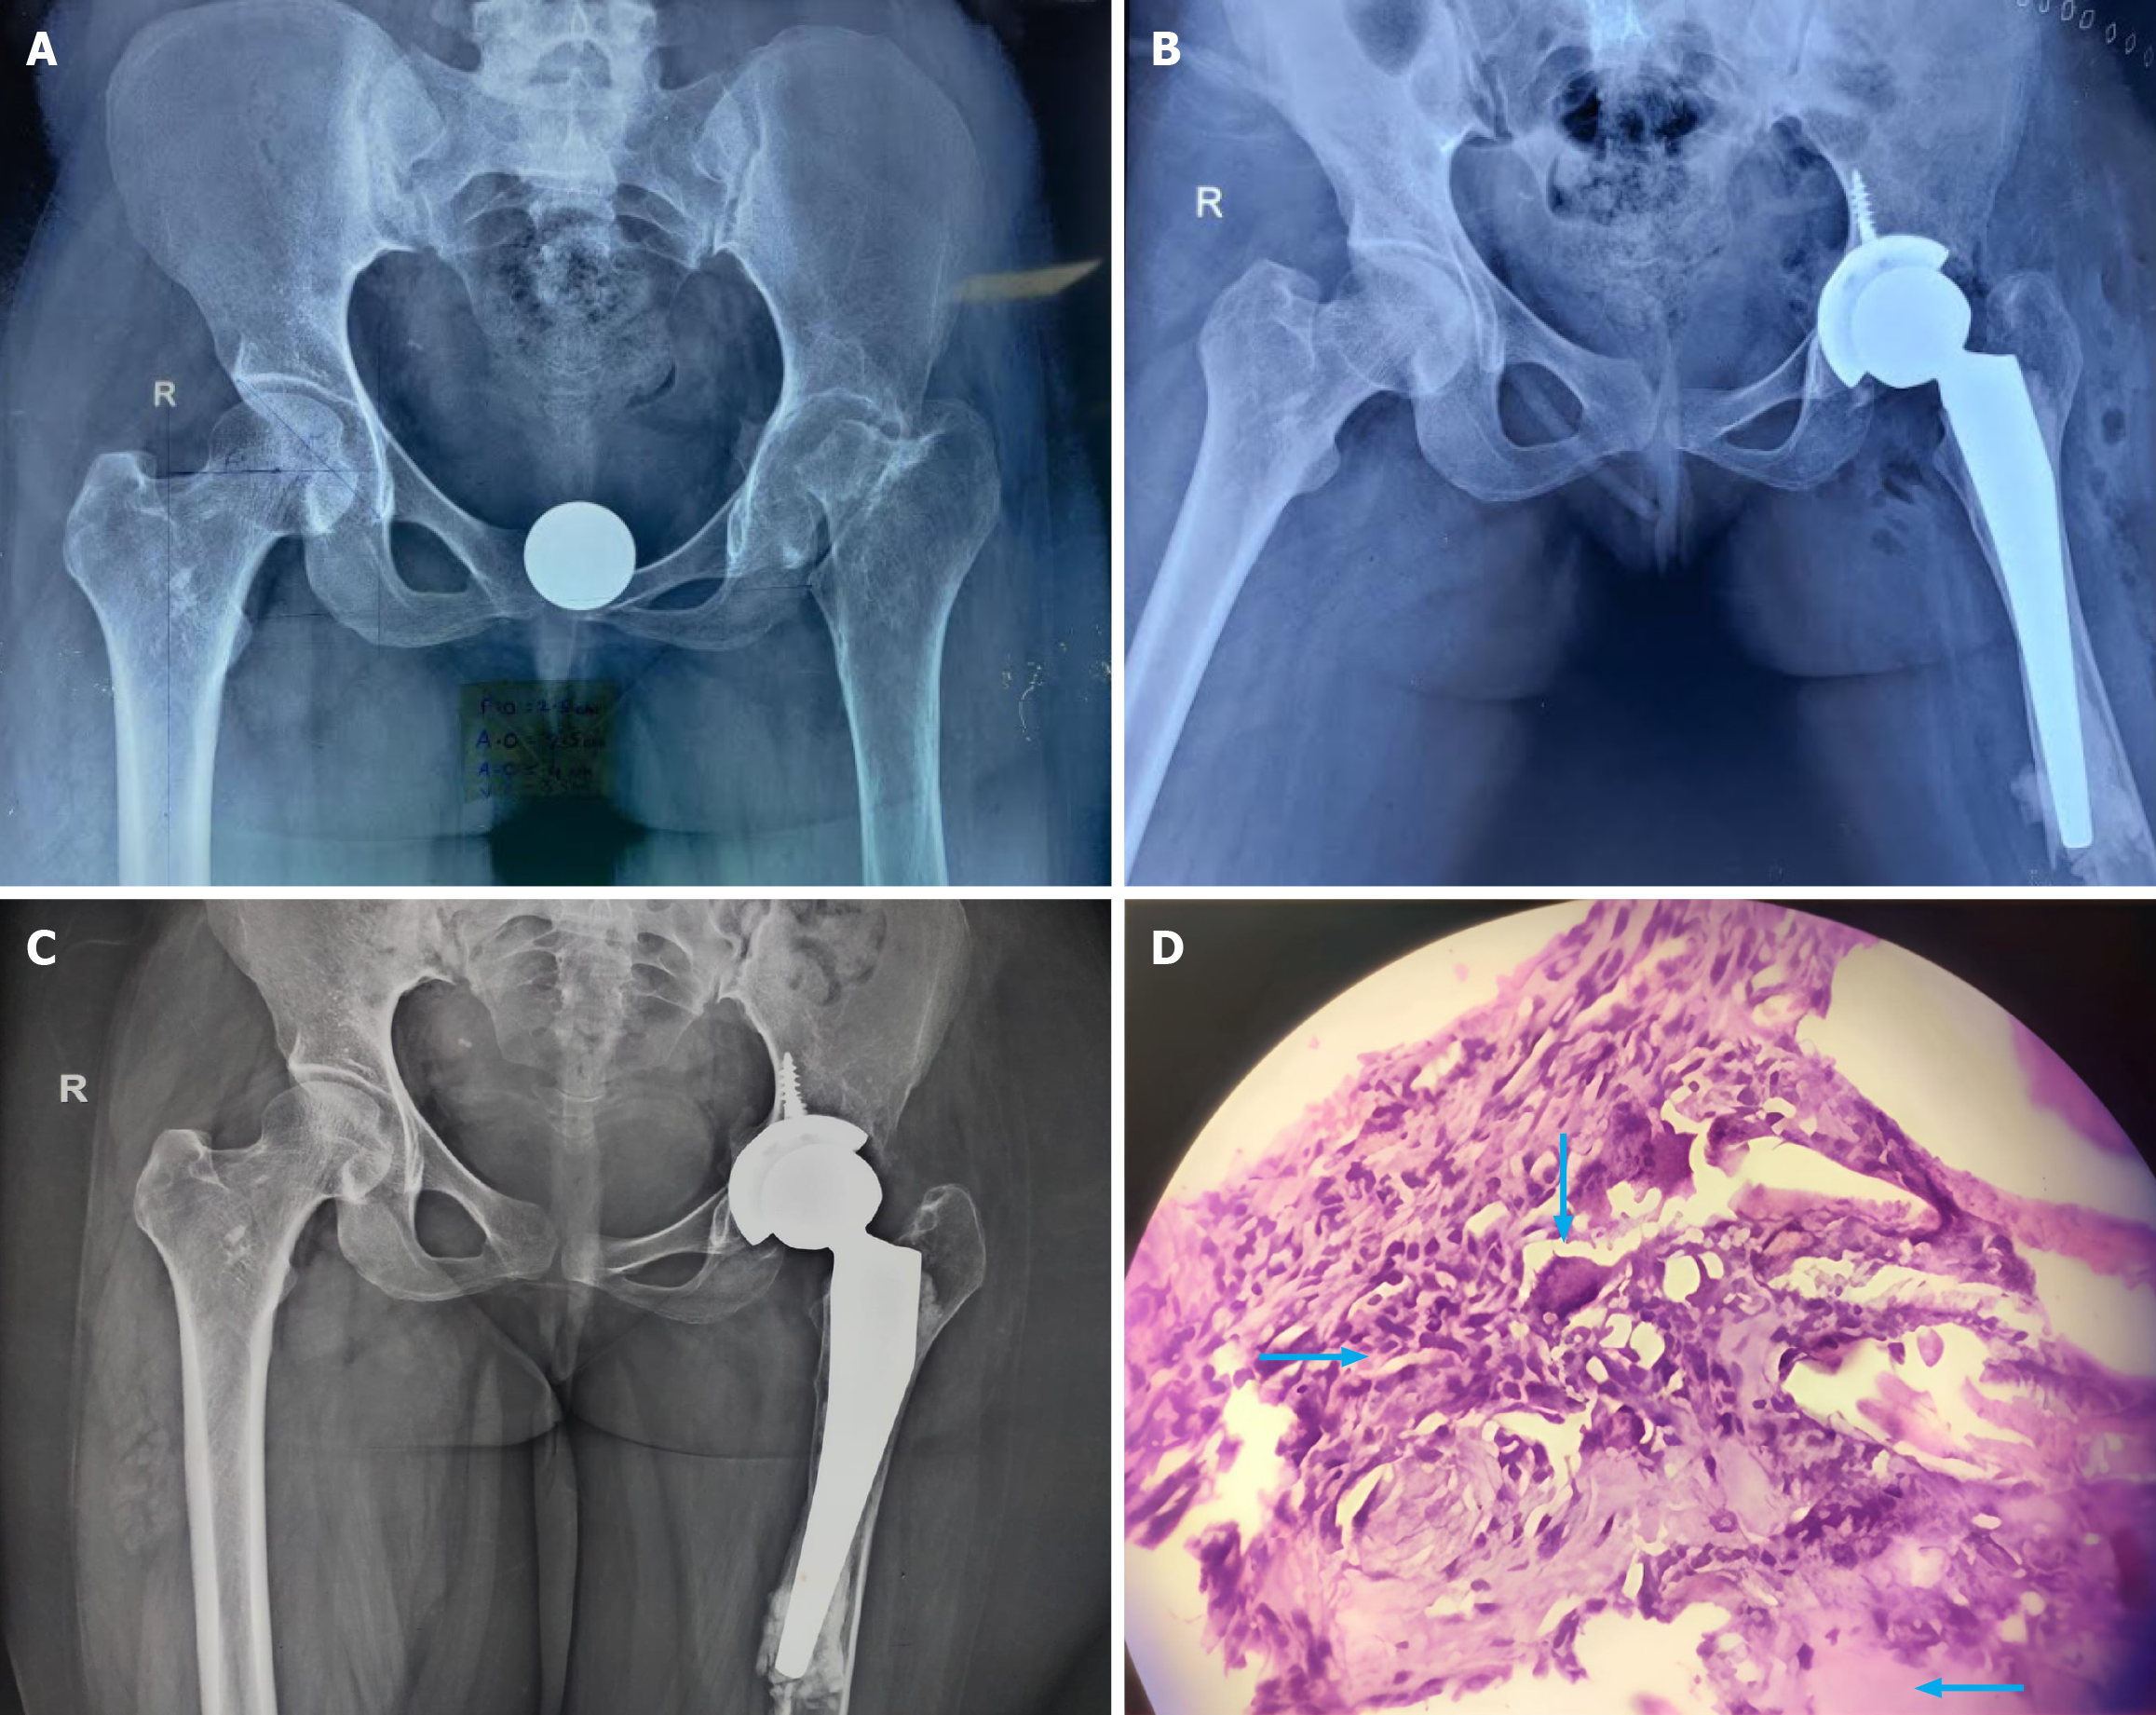

Cemented vs cementless THA

The heat released during cemented THA is expected to have a bactericidal effect; however, Shen et al[32] and Fang et al[36] have shown that, rather than the type (cemented vs. cementless) of THA, it is the meticulous debridement and an effective ATT that are detrimental to the outcome. In our study of 21 patients, the majority (n = 18) were cemented (Figure 3), and 2 had uncemented THA (Figure 4). Most of the patients in the present study were without health insurance, and financial constraint was the primary reason for performing a cemented THA, although many had satisfactory bone quality at the time of surgery. A brief comparison of our study with similar studies regarding the type of arthroplasty has been shown in tabular form (Table 5).

Figure 3

Figure 3 The imaging information of a 48 years old male with advanced active stage 3 tuberculosis left hip. A: Pre-operative pelvic radiograph (anteroposterior view) of the patient; B: Immediate post-operative radiograph of the patient following cemented total hip arthroplast; C: Follow-up radiograph of the patient at 32 months; D: Satisfactory clinical outcome of the patient at 32 months follow-up.

Periprosthetic fracture

Liu et al[37] observed juxta-articular osteoporosis due to ongoing active disease as well as generalized osteoporosis resulting from prolonged recumbency due to advanced joint destruction; this could be a risk factor for periprosthetic fracture in these patients. One of our patients (a 27-year-old female) had an intraoperative breach of the posteromedial aspect of the femur, which was only noticed on postoperative radiographs (Figure 5). The patient was reluctant to undergo an immediate revision; she was advised 4 weeks of bed rest before ambulation. One must be cautious while applying THA components in these patients; intraoperative use of an image intensifier is advisable to detect untoward periprosthetic fractures.

Figure 5

Figure 5 Imaging information of a 27 years old female with advanced active stage 3 tuberculosis left hip. A: Pre-operative pelvic radiograph (anteroposterior view) of the patient; B: Immediate post-op radiograph of the patient following hybrid total hip arthroplasty, showing breach in the femoral cortex; C: Radiograph of the patient at the time of last follow-up; D: Tuberculosis hip confirmed on light microscopy, hematoxylin and eosin-stained section from the biopsy material shows clusters of epithelioid histiocytes along with Langhans giant cells in a background of chronic inflammatory infiltrate and foci of caseous necrosis (100 ×). Blue arrow (downfacing): Langhans giant cells, blue arrow (right facing): Epithelioid histiocyte, blue arrow (left facing): Necrosis.